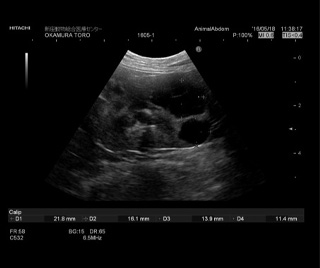

腎臓のエコー写真です、のう胞という液体貯蔵が腎臓の中に見られます。 |

未だに治療法が無いと言われる多発性腎嚢胞に対して、当院では再生医療による治療に取り組んでおります。

まだ症例が少なく、確実なデータの集積には至っておりませんが、実施した症例の嚢胞には縮小が見られ、治療効果をあげております。